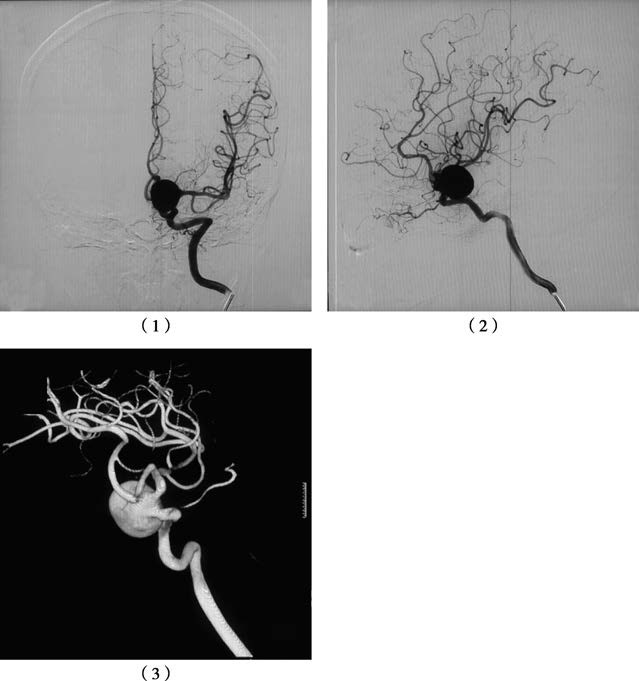

Figure 2 Giant aneurysm of the left internal carotid artery-posterior communicating segment on DSA

1, Anteroposterior view of the left internal carotid artery.

2, Lateral view of the left internal carotid artery.

3, Three-dimensional angiography for detailed visualization.